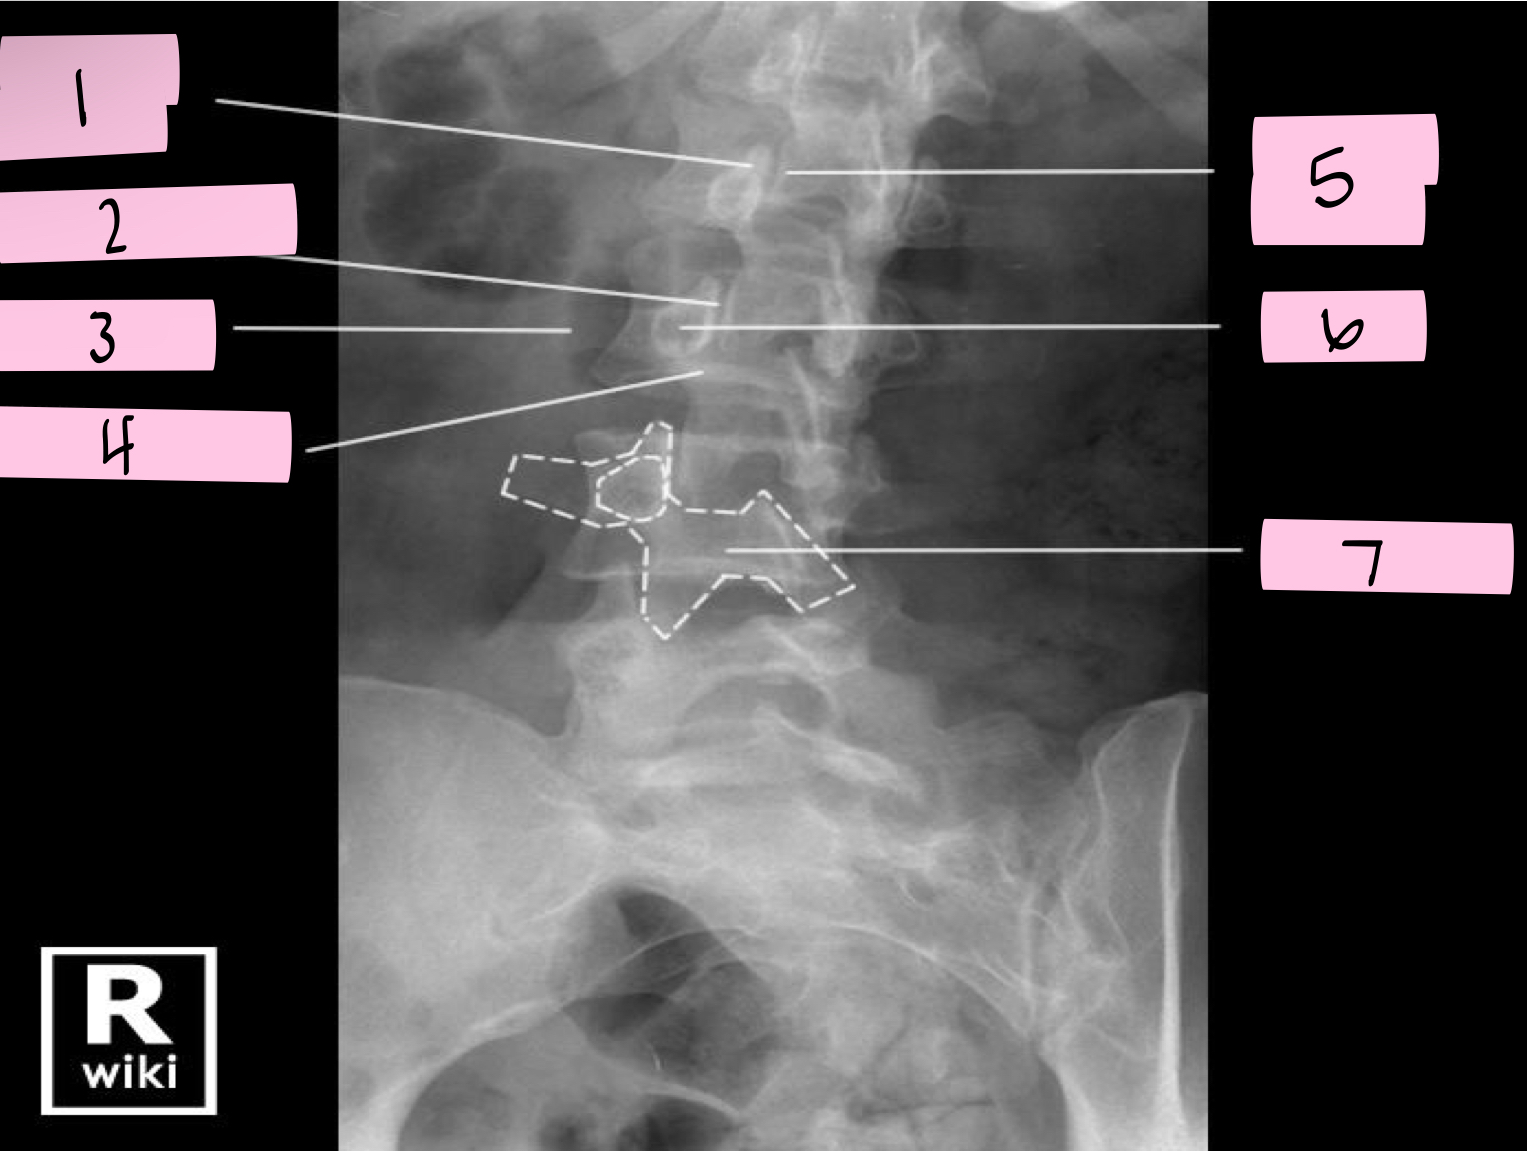

What is 1 pointing to?

Nose- Transverse process

What is 2 pointing to?

Eye- Pedicle

What is 3 pointing to?

Neck- Pars interacticularis (isthmus)

What is 4 pointing to?

Foreleg- Inferior articular process

What is 5 pointing to?

Ear- Superior articular process

What is 6 pointing to?

Tail- Superior articular process of opposite side

What is 7 pointing to?

Body- Lamina and spinous process

What is 8 pointing to?

Hindleg- Inferior articular process of opposite side